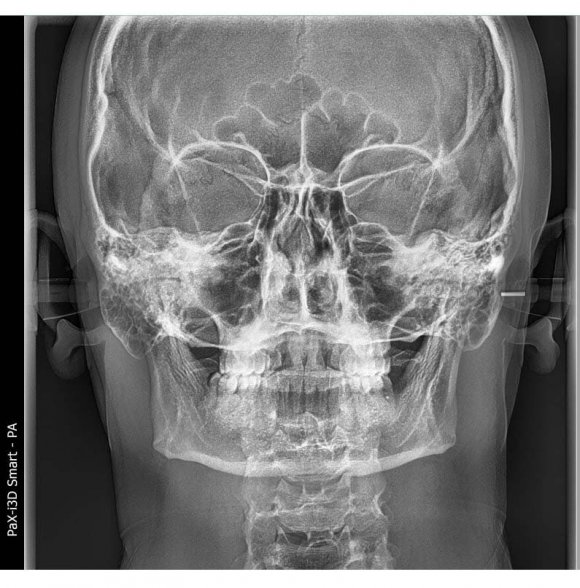

The study that we want to cover in this article is a frontal (front-back projection) cephalogram [4], which shows the main indicators in the detection of anomalies in the transverse direction. Problems in the transverse direction of the maxillofacial area can also cause serious problems for orthodontists, and it is these problems that are most likely to cause relapse [5]. Vertical anomalies are easy to detect in lateral cephalometry [6], but vertical asymmetry on both the right and left sides of the face can be fully analyzed only in frontal projection cephalometry [7]. In the literature on orthodontic diagnosis, there is very little information on the schematic measurement of the dimensions of the face in the transverse direction, that is, the data of the face jaw area at the developing period in the sagittal and vertical directions have not been sufficiently studied [8,9]. In this study, we will clearly explain the uniqueness of the growth of the face in the vertical direction in people with long faces (dolichocephals) -mainly the development of the lower part of the face, and the increase in the angle of the lower jaw [10]. In determining the vertical dimensions of the face, the transverse growth indicators of the upper and lower jaws are primary important [11]. Therefore, this study will be of great help in determining frontal cephalogram parameters for assessing the symmetry of facial bones and teeth.

We described the comparison of the upper and lower jaws in such a perfect way that it is impossible not to use these indicators during this research. To determine the relationship of the upper and lower jaws to each other, a line is drawn from the Cg point to the J and Ag points on the right and left sides [9], the names of these points and lines are given in tables 1 and 2, and pictures 1 and 2. The right J and left J points are also connected, resulting in the formation of J-Cg-J triangle. Similarly, a horizontal line is drawn from the right Ag to the left Ag point and the triangle Ag-Cg-Ag is formed. These triangles are divided into two using MSR and four triangles: right J-Cg-MSR and left J-Cg-MSR; Ag-Cg-MSR and Ag-Cg-MSR are produced (Figure1). In this article, the authors compared the length of the sides of the triangles and evaluated their symmetry [6,9,10]. The indicators of the upper and lower jaw symmetry of representatives of the Uzbek population were determined, compared the indicators of men and women Grummons indicators (table 3). We compared the indicators of "comparison of the upper and lower jaws"of the representatives of the Uzbek population with normal physiologicalbite with the results of the average indicators of men and women. The J-MSR index for Uzbeks is 31.72±0.18 mm on the right and 31.69±0.17 mm on the left; in men, right 32.07±0.21mm. and left 31.96±0.21mm; right 31.25±0.25mm in women and left 31.33±0.27mm. equal to, and no significant difference was found when they were compared with each other or compared with the average values (P>0.05). Ag-MSR index in men is 42.6±0.25mm right and 42.49±0.29mm left; Ag-MSR index of women is 39.98±0.37mm right and 41.0±0.35mm left. is equal to It was found that the average of the Ag-MSR indicator of Uzbeks is equal to 41.49±0.25 mm on the right and 41.86±0.24 mm on the left. Now, when we compared Ag-MSR values of women and men with respect to mean Ag-MSR values, only female Ag-MSR R values were significantly different (P<0.05). When the Ag-MSR indicators of men and women were compared, it was found that there was a reliable difference between the Ag-MSR R indicator of men and the Ag-MSR R indicator of women (P<0.05). The average of the Cg-J indicator of Uzbeks is 68.82±0.47 mm on the right and 68.63±0.46 mm on the left. Cg-J index in men is 71.09±0.58mm right and 70.87±0.55mm left; in women, the right is 65.7±0.45mm and the left is 65.55±0.49mm. When comparing the Cg-J index of women and men, there are reliable differences in the Cg-J index of men compared to the Cg-J index of women (P<0.05). Now, when comparing the Cg-J index of women and men to the average of Uzbeks, a reliable difference was found only in men's Cg-J index compared to the average Cg-J index (P<0.05).

Figure 1: Points (Landmarks) used in Maxilla-Mandibular Relationship Indicators of the Frontal Cephalogram

Figure 2: Comparison of upper and lower Jaws (Maxillo -Mandibular Comparison)